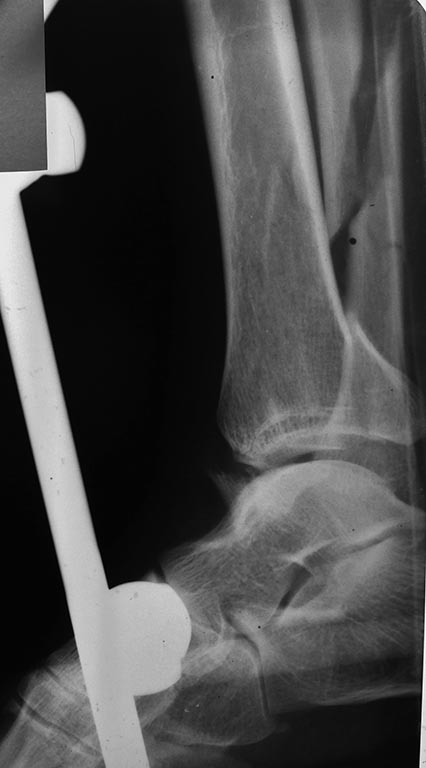

Травма голеностопного сустава 44С3 помогите определиться с оперативной тактикой

Пациентка 49 лет, повышенного питания, получила травму поскользнувшись на улице, сразу поступила к нам,

при поступлении наложен стержневой авф, прошло 5 суток, отек умеренный, будем готовы к пятнице к операции. Думаем 1/3 трубка на наружную, фиксация синдесмоза, вопрос в медиальной лодыжке и заднем крае, коллеги, подскажите какой фиксатор предпочтительнее, заранее благодарен, Дмитрий.

P.S: провести кт нет возможности и ни под каким углом(